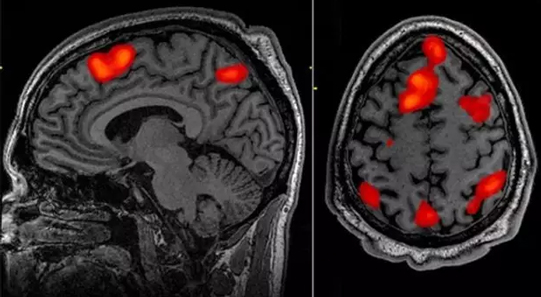

• 医健资讯|fMRI分析爆重大缺陷 9年前

作者们还注意到,目前的公开数据行动让任何人都可以容易地追溯研究,并以新的思路更小心地重新分析原始研究的数据。但是大多数已...